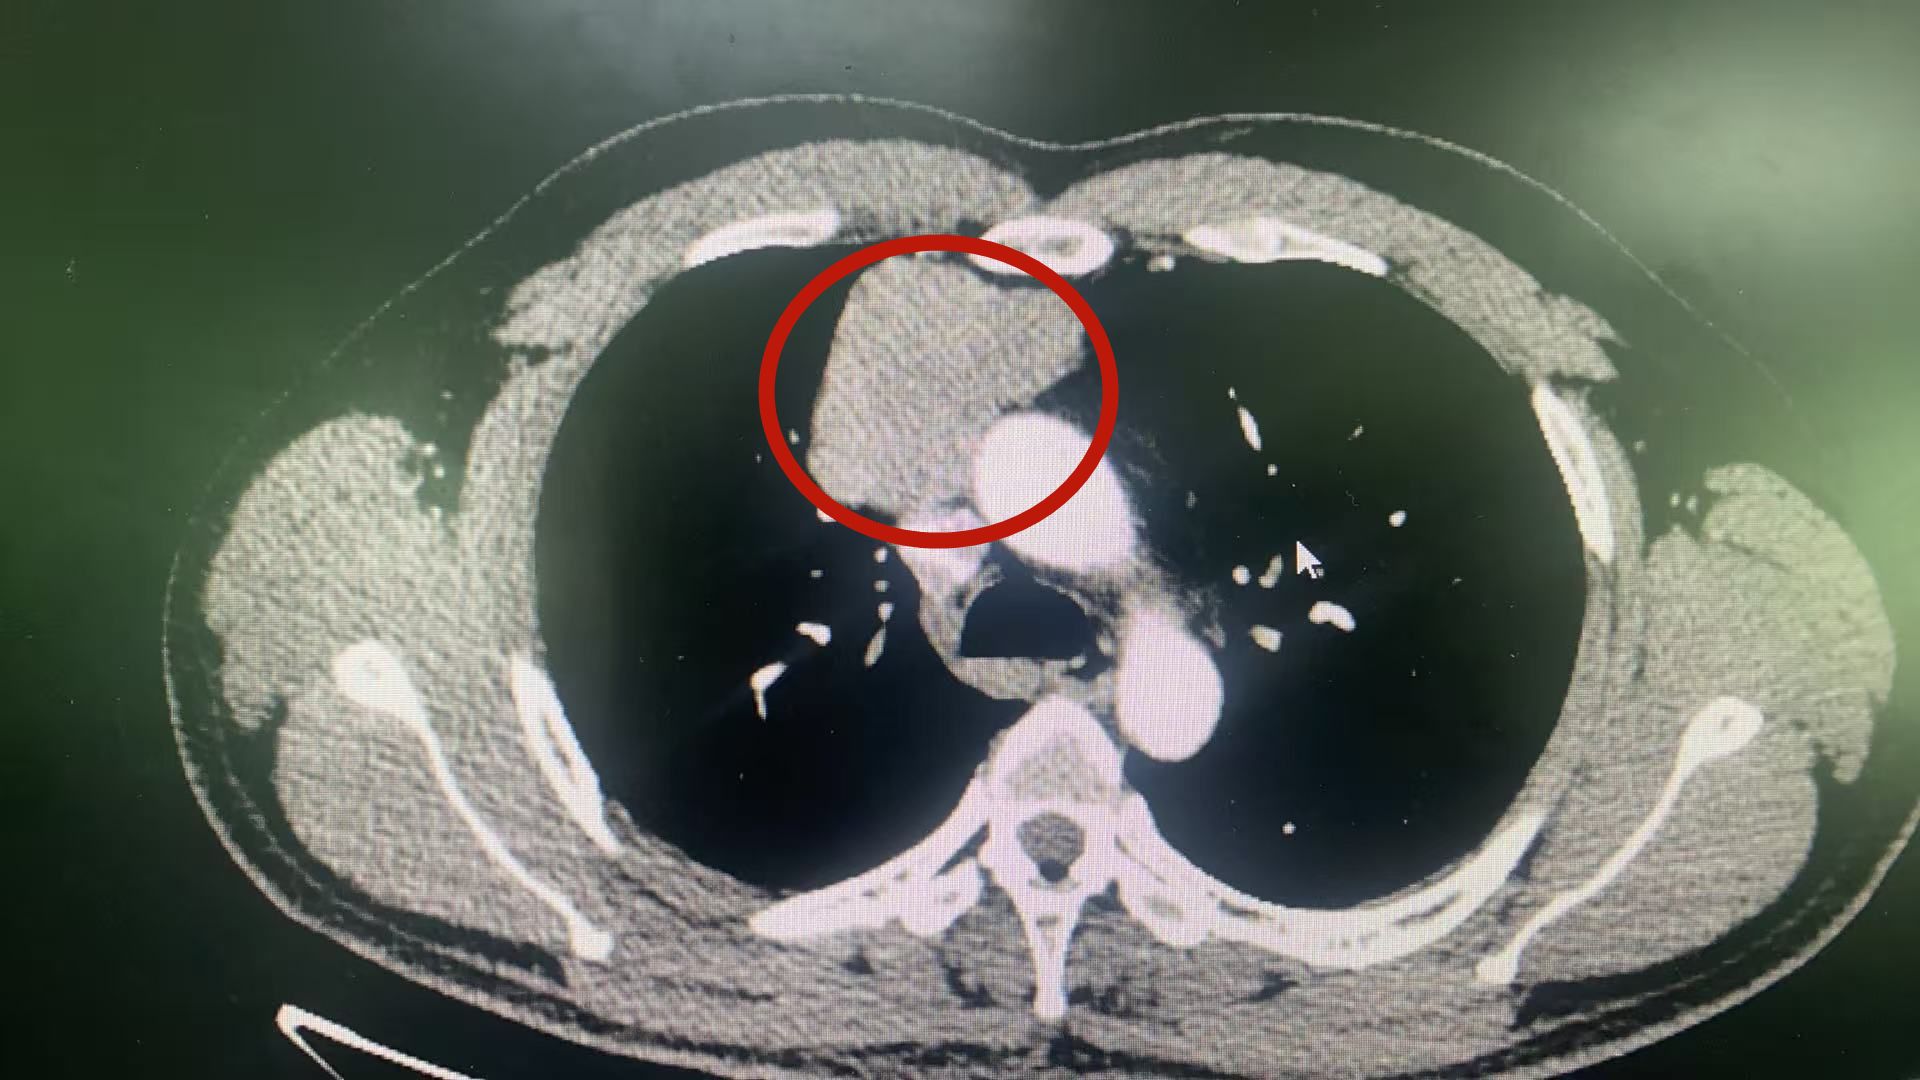

3厘米切口巧除心脏旁80mm纵隔肿瘤

仅通过一个3厘米的切口,完整切除紧邻心脏大血管的80毫米巨大纵隔肿瘤。近日,第五附属医院胸心外科团队成功完成一例高难度胸腔镜微创手术,实现了根治性切除与快速康复,充分展现了医院在复杂纵隔肿瘤微创治疗领域的技术水平。辗转求医,巨大肿瘤成难题龚先生(化名)今年36岁,此前因身体不适于外院检查,发现右前上纵隔存在直径约80mm的巨大占位病变。此纵隔位置深邃,四周紧密环绕…